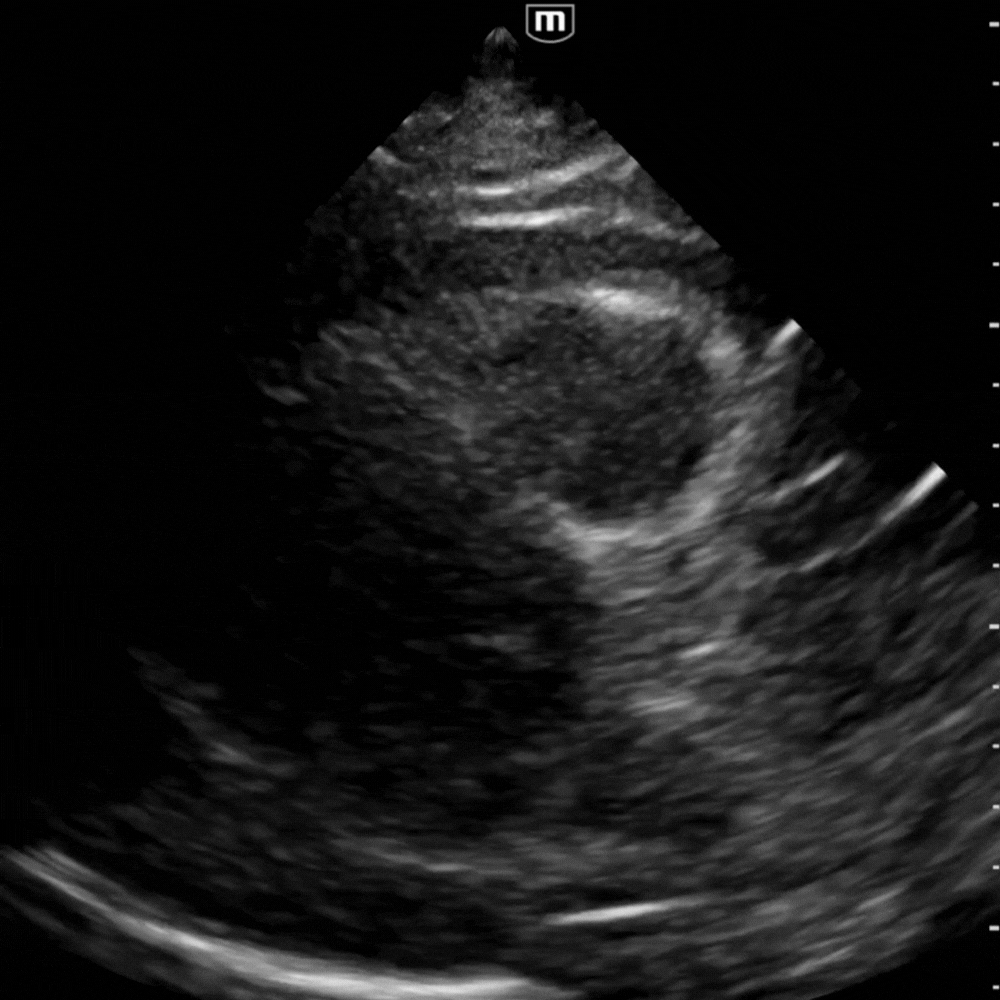

Vue apicale quatre cavités

Montre la circonférence du liquide et le balancement du cœur (“swinging heart”) lorsque le volume est important.

Vue utile pour juger la cinétique globale et confirmer le collapsus diastolique du VD.